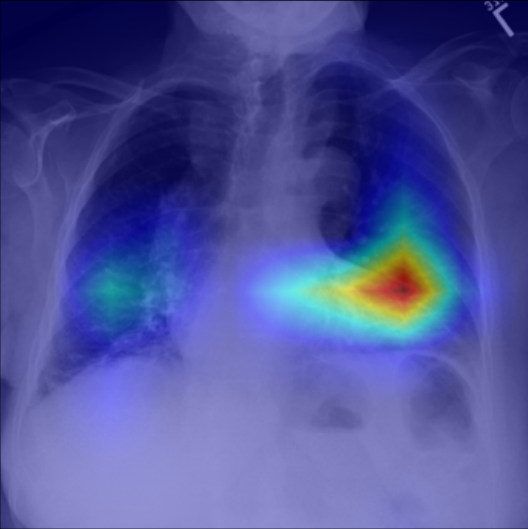

Refer to caption

Figure 5: Visualization of attention map in PLAN on MS-CXR. The red boxes indicate the corresponding ground truth of grounding. Highlighted pixels represent higher activation weights correlating specific words with regions in the image.

IV-B1 Phrase Grounding

Phrase grounding associates textual phrases (e.g., disease descriptions or anatomical terms) with corresponding regions in medical images, offering precise diagnostic insights and enhancing model interpretability. Table II presents the phrase grounding results on the MS-CXR dataset. Using the Contrast-to-Noise Ratio (CNR) [27] as the evaluation metric, PLAN achieved the highest CNR across eight disease categories, outperforming MGCA and PRIOR. Heatmaps generated with Grad-CAM (Figure 4) further illustrate PLAN’s ability to accurately localize lesion sites and align disease-related phrases with image regions. Additional comparisons with baseline methods can be found in Figure 5. These findings highlight PLAN’s superior precision and interpretability in phrase grounding tasks.